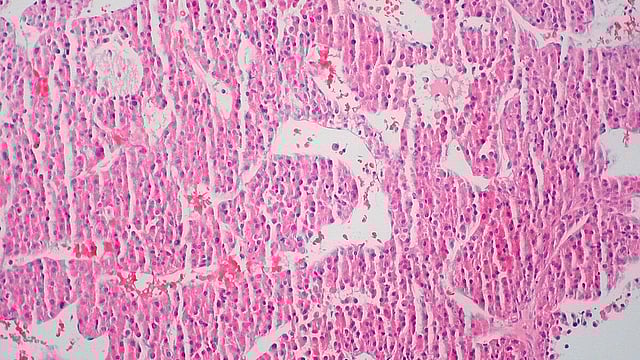

T-MBs (Targeted Microbubbles) are specially engineered ultrasound contrast agents designed to selectively bind to cancer cells. In liver cancer, T-MBs are conjugated with antibodies that target B7-H3, a protein overexpressed on liver tumor cells but limited in healthy tissues. Ed Uthman - Wikimedia Commons images